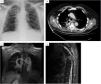

Physical examination was notable for crackles on auscultation in the upper and middle fields of the right lung, as well as spastic paraparesis with normal rectal tone. Blood test showed increased C-reactive protein 15mg/dL (reference range 0.5–1). Chest X-ray showed right paratracheal infiltrates (Fig. 1A). Chest CT showed cavitating right lung consolidation and crush located at T5-T6 (Fig. 1B). Thoracic spine MRI showed lung-spinal fistula and signs suggestive of spondylodiscitis (Fig. 1C and D).

(A) Chest X-ray: right paratracheal infiltrates. (B) Chest CT: right lung consolidation occupying the azygo-esophageal recess, with aire-fluid level and calcium deposits, as well as a marked crush and destructuring located at the T5-T6. (C) Thoracic spine MRI (coronal): central necrotic-cystic zone occupyping the disc space of the T5-T6 and fistulous communication with the adjacent right lung injury. (D) Thoracic spine MRI (sagittal): diffuse gadolinium enhancement and kyphotic deformity with canal stenosis located at the T5-T6.